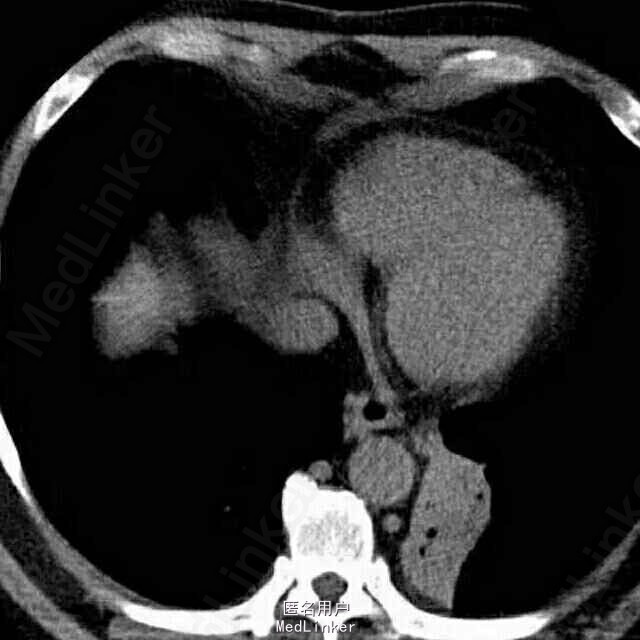

女,50岁。 间断咯血25年余,加重1月,行肺部增强CT。

患者胸部增强CT及血鬼重建影像学表现包括:边界清晰、病变有主动脉分支供血、病变静脉引流入肺静脉。

考虑影像学诊断为:肺隔离症

左肺下叶内前基底段脊柱旁可见斑片影,边界清晰,其内可见支气管气相,平扫密度尚均匀,增强后病变内强化不均匀,可见多发血管影,血管重建示病变由主动脉弓及降主动脉迂曲增粗的小分支供血,可见一直粗大静脉引流入左肺静脉。根据病变部位,供血动脉来源于体循环,静脉引流入肺静脉,此例为典型肺隔离症,已被术后病理所证实。 肺隔离症是一种先天性肺发育畸形,主要特征是部分胚胎肺组织与正常肺组织隔离,病变肺组织的动脉供应由体循环直接分出的动脉分支供应,静脉回流至肺静脉或体循环。尽管其表现多种多样,体动脉向肺组织供血为其最特征表现。常分为叶内型及叶外型2种,最常见为叶内型,多为体动脉单支血管供血,无单独胸膜包裹。叶外型有单独胸膜包裹,多位于膈肌下,由肺或体血管供血,血管较小,多伴有其他先天畸形。本例为叶内型,隔离的肺组织易反复发生感染,出现相关临床表现。 肺炎主要表现为肺实变或不张,常伴有病变周围斑片或淡片影,边界可不清晰,临床症状有助于诊断。 肺癌侵犯病变内及周围血管、支气管,造成支气管闭塞伴远端阻塞性炎症,肺门及纵隔常见肿大淋巴结。 支气管扩张伴感染时可见扩张的支气管,可为管状、串珠样或囊泡状,病变周围感染呈斑片影,边界欠清晰。